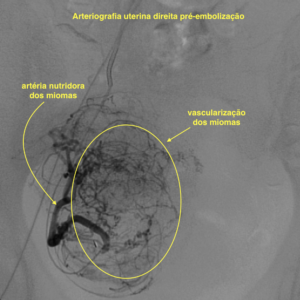

A Embolização é realizada durante um procedimento de arteriografia por meio de cateterismo. Uma pequena punção com anestesia local é realizada na virilha ou no braço, e então, um pequeno cateter é introduzido até dentro das artérias que levam o fluxo de sangue para o útero (artérias uterinas). Em seguida, pequenas partículas sintética são injetadas no interior desses vasos, a fim de obstruir o seu fluxo sanguíneo. Com isso, o útero e os miomas passam a receber pouca irrigação e, consequentemente, reduzem o seu tamanho e melhoram os sintomas. O procedimento é realizado em ambiente hospitalar, com anestesia, e a paciente costuma ficar internada por 1-2 dias.

Arteriografia uterina direita durante procedimento de embolização de mioma uterino